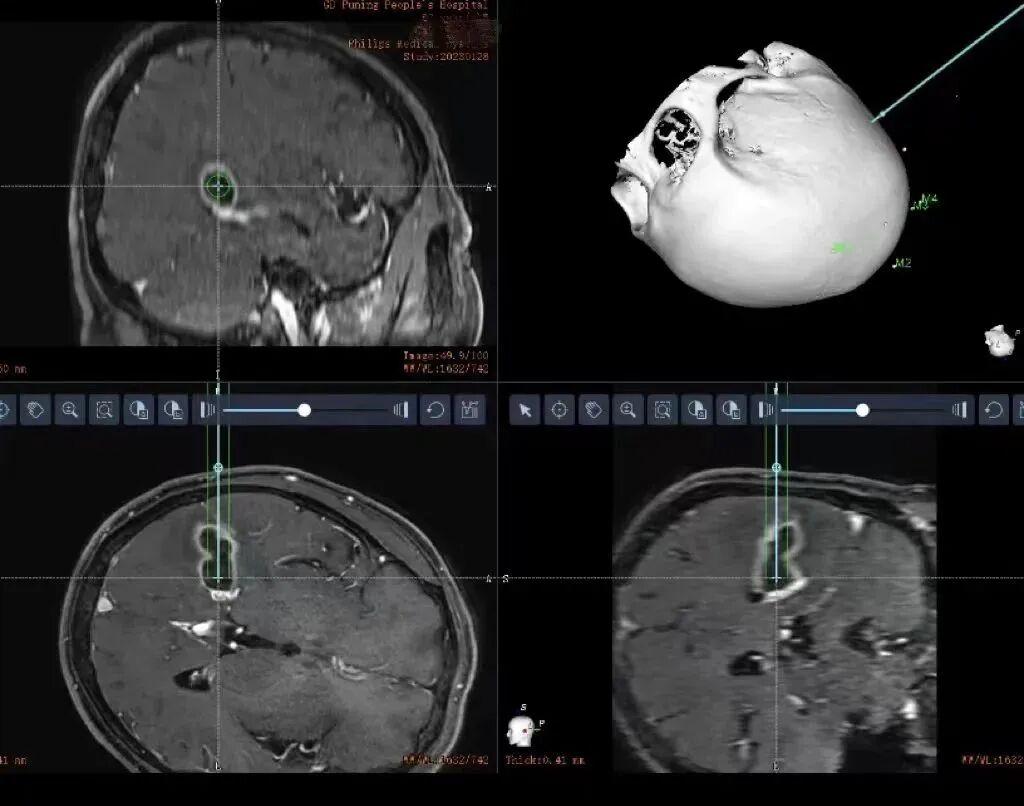

术前,谢树浩医师在患者头部贴上特制的标记后陪同前往CT室行头颅CT检查,在机器人手术计划系统上融合了患者的磁共振、CT等影像检查,避开了重要脑回、血管等重要结构,选择最佳的精准穿刺路径。在黄雪钦副院长指导下,王晓东主任医师治疗团队为陈老伯行机器人手术治疗。手术从机器人的注册、消毒、钻孔、置管一气呵成,置入引流管后,引流管内引流出大约6ml乳白色的脓液,明确了不是恶性肿瘤是脑脓肿的诊断,而且做到了精准无误的脓肿引流。术后陈阿伯清醒后拔除气管插管安返病房,复查头颅CT和mr显示脓肿清除满意。后期根据脓肿的细菌学检查进行下一步规范的抗感染治疗。

术前CT和MR多模态影像融合,设计最佳穿刺路径